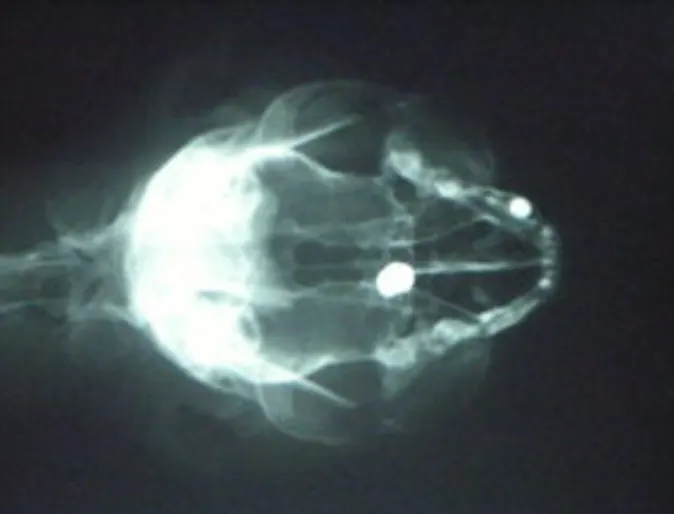

Cat Shot In Head With Pellet Gun

This is an interesting case but unfortunately true. Tiddy Tat was referred to us from a veterinary clinic in Welland. Tiddy Tat is a very cute 1 and 1/2 year old female cat that was a stray for almost a year before her compassionate owner was able to adopt her once she lost her fear of people.